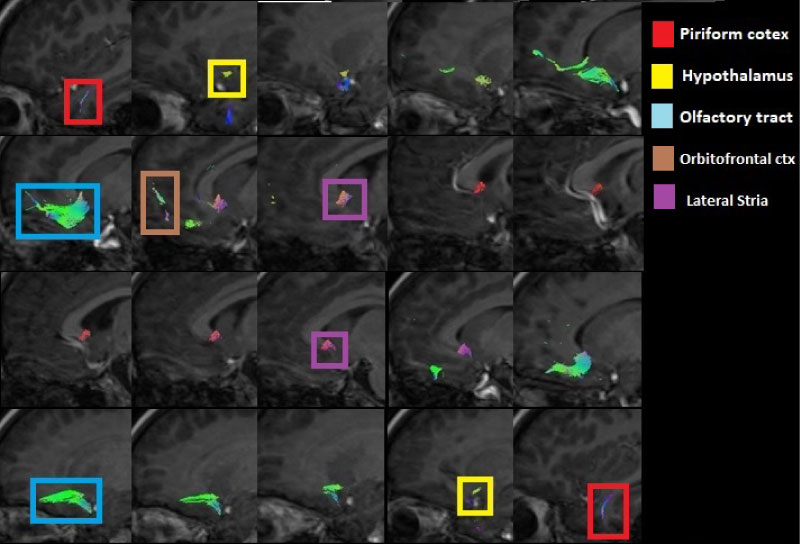

The olfactory tracts obtained are projected directly towards the piriform lobe located at the level of the hippocampus in the temporal cortex in the frontal part of both hemispheres (Figure 3, Figure 4 and Figure 5). There are tracts between the amygdala and the olfactory tract.

Figure 3: Sagittal view of the olfactory tracts (left to right) showing the tracts corresponding to the piriform cortex, the hypothalamus, the olfactory tract from the olfactory bulbs, the orbitofrontal cortex and the lateral stria. View Figure 3

Figure 4: Axial view of the olfactory tracts (inferior to superior) emphasizing the piriformis cortex, the olfactory bulbs, the olfactory tract of the olfactory bulbs, the orbitofrontal cortex and the lateral stria. View Figure 4

Figure 5: Coronal view of the olfactory tracts (anterior to posterior) emphasizing the piriformis cortex, the olfactory bulbs, the olfactory tract of the olfactory bulbs, the orbitofrontal cortex and the lateral stria. View Figure 5

Direct and indirect olfactory pathways

There are tracts that connect the piriform lobe with the orbitofrontal cortex: The indirect way that passes through the thalamus, which is involved in the perception and discrimination of smells, and the fibers that surround the temporal lobe of the lateral ventricle and run through the sub lenticular white matter (Figure 3, Figure 4 and Figure 5).